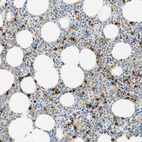

Immunohistochemical staining of human lung shows moderate to strong cytoplasmic positivity in macrophages.